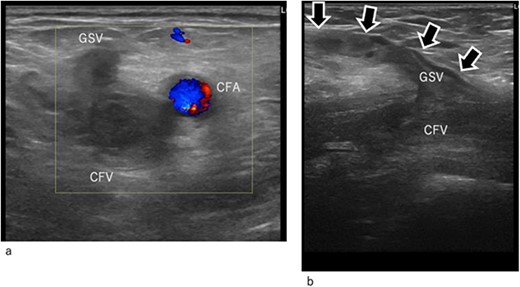

On postoperative Day 9, the patient experienced pale, cold pain in the left lower extremity (Fig. 1a). The symptoms progressed rapidly and at 4 h after their onset, the patient could not walk because of pain and paralysis in the left lower extremity. Ultrasonography revealed total occlusion of the left deep veins from the common iliac to the popliteal vein. Moreover, occlusion was also observed in superficial veins, including the great saphenous vein (GSV) and its branches (Fig. 2a and b). Arterial ultrasound examination showed no thrombus or occluded lesion but impaired pulsatile flow in the left lower extremity. Blood tests revealed very high levels of D-dimer (25 ng/mL) and fibrinin/fibrinogen degradation products (100 μg/mL).

Duplex ultrasound image at arrival. (a) Transverse image. (b) Longitudinal image. The common femoral and GSV (arrow mark) are occluded by thrombi. CFA, common femoral artery; CFV, common femoral vein; GSV, great saphenous vein.